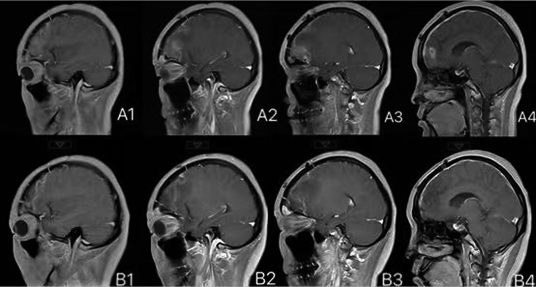

2020年8月,一名38岁、脑瘤术后拟行放疗的女性患者来到河南省人民医院。 患者2020年7月因前额部持续性胀痛伴加重,自行口服止痛药效果欠佳就诊于当地医院。颅脑CT检查结果提示:右额叶占位性病变。医生考虑脑膜瘤,建议进行手术治疗。后来,患者就诊于某三甲医院,进行头颅MRI(磁共振)检查,结果提示:T1呈混杂等低信号,T2呈混杂等高信号,FLAIR(磁共振成像液体衰减反转恢复序列)呈混杂等高信号,DWI(弥散成像序列)呈低、等稍高信号,ADC(表观弥散系数)呈高、等低信号。 为患者注射钆喷酸葡胺后进行扫描,可见明显不均匀强化。MRI检查结果提示:右侧额部占位性病变,考虑脑膜瘤可能性大,孤立性纤维瘤及其他病变不除外。 患者2020年7月31日在河南省人民医院全麻下进行“右额叶肿瘤切除术”。 术后病理检查结果提示:(右额叶)恶性肿瘤,考虑间叶性软骨肉瘤(图1),建议省级专家会诊。免疫检查结果提示:CD56(NK细胞,+),CD99(兔白细胞分化抗原,+),CK(AE1/AE3)(-),Desmin(结蛋白,-),EMA(上皮细胞膜抗原,-),GFAP(神经胶质酸性蛋白,-),Ki67(热点区约30%+),Myogenin(肌细胞生成素,-),Olig-2(+),S-100(-),STAT6(人信号传导转录启动因子6,-),SYN(突触素,-),Vimentin(波形蛋白,-),SMA(平滑肌肌动蛋白,-)。在低倍放大镜下,可见病理切片由大的未分化小细胞、小且圆形或短的梭形细胞和小细胞质组成。细胞核呈圆形或卵形,染色较深,核仁不明显,中间可见少量透明软骨的小岛,软骨分化相对成熟(图1右)。 2020年8月19日,对这个病例,相关专家会诊后报告如下:(右额叶)恶性肿瘤,符合间叶性软骨肉瘤的诊断。 术后,患者的头颅磁共振(3.0T)检查结果提示:与2020年8月27日所拍的片子对比,术区出血灶较前吸收减少;额窦病灶缩小。患者进行了3个周期的化疗。 术后患者间断性头痛,并伴有双侧眼周肿胀。患者进行头颅3.0T磁共振平扫+增强,结果提示:右额叶见斑片状短T1、长T2信号影,FLAIR呈高信号,DWI呈高信号,增强扫描可见局部轻微强化,周边可见水肿带环绕,右侧脑室前角稍受压,中线结构居中。 接诊患者后,我们认为对该患者的诊断有疑点: 1.中枢神经系统缺乏间叶组织,软骨肉瘤的诊断是否成立。 2.术后患者肿瘤占位解除,但患者仍间断性头痛,双侧眼周肿胀,仅用术后改变来解释是否合理?是否存在残余肿瘤? 于是,我们再次阅读患者术前、术后的头颅MRI片,发现患者存在额窦病变,并且在术前、术后MRI影像中未见明显变化。 我们请河南省人民医院健康管理中心的影像专家李永丽会诊。李永丽也认为患者额窦病变与颅内部分影像表现一致,应考虑手术残留病变。但是,软骨肉瘤恶性程度低,对放化疗敏感性低。目前,患者症状明显、残留病灶存在,不同意再次手术,无放疗禁忌证,于2020年9月7日进行放射治疗。 我们给予处方剂量额窦病变PGTV(原发肿瘤计划肿瘤靶区):64Gy(辐射计量单位),PTV1(预防区计划靶区1):60Gy,PTV2(预防区计划靶区2):54Gy(图3),共30次,每周5次;患者在放疗过程中耐受性可,前额疼痛、肿胀症状明显缓解后出院;放疗结束后,多次进行药物治疗。术后1年病情无明显进展。目前,术后放疗和化疗的过程已完成,患者无不适,耐受性尚可,定期复查。患者仍在随访观察中,一般情况好,前额肿胀、疼痛等症状消失,影像检查结果提示:病灶无进展。 软骨肉瘤是骨肿瘤中常见的恶性肿瘤,是由染色体异常引起的软骨组织疾病。迄今为止,颅内软骨肉瘤的起源仍不清楚。颅内间叶性软骨肉瘤是一种罕见的中枢神经系统恶性肿瘤,通常发生于年轻人,约占颅内肿瘤的0.15%。原发性颅内软骨肉瘤绝大多数起源于颅底,预后较差,局部复发的可能性较高。有报道说,与手术结合术后辅助放疗相比,单纯手术似乎是无效的治疗策略。因此,手术结合术后放疗,患者可获得最佳的生存时间。相关研究发现,仅接受手术治疗的软骨肉瘤患者的5年死亡率为26%,而实施术后辅助放疗则使死亡率大幅降低至4%。 近期,许多研究指出,精细的手术切除加上术后放疗,可为这些患者提供最佳的长期预后。相关专家在2002年开展的研究发现,术后放疗可能对这些患者有益。而一项关于此类问题的研究,在2007年也明确指出,放疗是治疗软骨肉瘤的重要辅助疗法。我们为该患者选择术后辅助放疗,使患者1年来保持较高的生活质量,未再出现前额胀痛症状,影像评估稳定。 (作者供职于河南省人民医院)